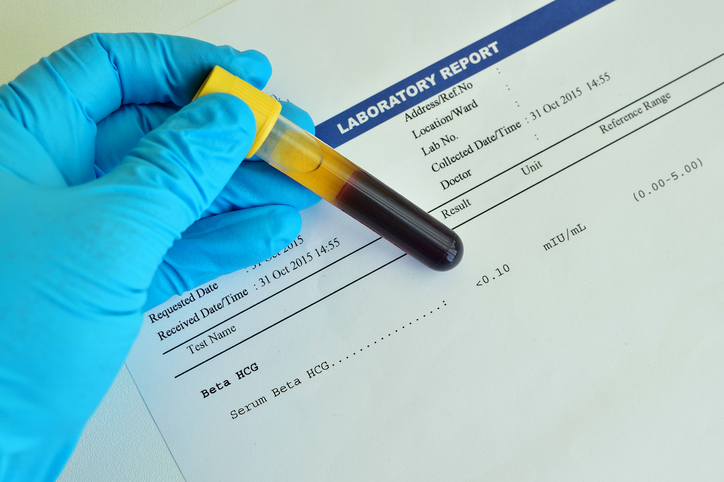

Beta negativa y embarazo es posible

Product Name: Test de embarazo positivo y no se ve nada en la ecografia dealsTest positivo y en ecograf a no se vio nada BabyCenter deals, Test positivos pero no se ve nada en la eco BabyCenter deals, Prueba de sangre positiva y en el eco no se ve nada BabyCenter deals, Prueba de sangre positiva y no se ve nada en la eco BabyCenter deals, prueba de sangre positiva no se ve nada en el ultrasonido deals, No se vio ni saco gestacional en la eco pero test positivo deals, Prueba de sangre positivo Nada en ecograf a BabyCenter deals, EMBARAZO DE 4 SEMANAS PRUEBA DE EMBARAZO POSITIVA Y NO SE VE SACO deals, En las pruebas de sangre sale que si estoy embarazada pero en el deals, prueba de embarazo positiva y no se ve nada en el deals, Prueba positiva en ultrasonido no se ve embarazo BabyCenter deals, Ecograf a de las 5 semanas No he visto al beb y ahora qu deals, Embarazo Anembrionario deals, prueba negativa pero eco positivo BabyCenter deals, La primera ecograf a qu pasa cuando no se ve el embri n deals, AS SE VE UN EMBARAZO DE 4 SEMANAS DE GESTACI N YouTube deals, EMBARAZO DE 4 SEMANAS PRUEBA DE EMBARAZO POSITIVA Y NO SE VE SACO deals, prueba de embarazo de eco B squeda de TikTok deals, C mo funciona un test de embarazo farmacias ecoceutics deals, EMBARAZO DE 4 SEMANAS PRUEBA DE EMBARAZO POSITIVA Y NO SE VE SACO deals, TEST DE EMBARAZO PUEDE HABER FALSO POSITIVO Y NEGATIVO Blog deals, Semana 6 de embarazo evoluci n del embri n y s ntomas deals, Semana 5 de embarazo desarrollo del beb y s ntomas en la madre deals, Todo lo que necesitas saber sobre el test de embarazo Matronastur deals, Respuesta a miguelinaperez431 gestaciondelocalizacionincierta es cuando tenemos un testdeembarazopositivo pero no vemos nada en la ecografia Para ello habra que determinar los niveles de bhcg en deals, Puede fallar el test de embarazo Natalben deals, Prueba de embarazo con linea tenue qu significa deals, Cuando hacer un test de embarazo tras una FIV Barcelona IVF deals, EDSONGCANO PRUEBA DE EMBARAZO POSITIVA Y ULTRASONIDO NORMAL deals, Test de embarazo positivo todo lo que debes saber deals, QU ES UN EMBARAZO QU MICO TEST EMBARAZO POSITIVO deals, S ntomas de embarazo pero test negativo posible falso negativo deals, L nea de Evaporaci n en el Test de Embarazo Gu a deals, Beta baja y embarazo evolutivo preguntas y respuestas deals, Carlos Zavala MD OBGYN zavalamdobgyn s videos with original sound Carlos Zavala MD OBGYN TikTok deals, Emocionante primera ecograf a del embarazo Cu ndo se hace y qu deals, Son fiables los tests de embarazo deals, Todo lo que necesitas saber sobre el test de embarazo Matronastur deals, Mi duelo MAMIfit ES deals, Ecograf a transvaginal Salud Femenina deals, Cu ndo podr a dar positivo un test de embarazo de alta sensibilidad deals, Errores al hacer un test de embarazo Puede dar un falso negativo deals, AS SE VE UN EMBARAZO DE 4 SEMANAS DE GESTACI N YouTube deals, C mo funciona el test que averigua la madurez pulmonar fetal deals, Respuesta a albitamansanita2 Tienes un examen de embarazo deals, Beta negativa y embarazo es posible deals, El ultrasonido temprano en el embarazo deals, INCERTIDUMBRE AGRIDULCE EN NAVIDAD Laia Rovira deals, Cuando hacer un test de embarazo tras una FIV Barcelona IVF deals, Todo lo que necesitas saber sobre el test de embarazo Matronastur deals.